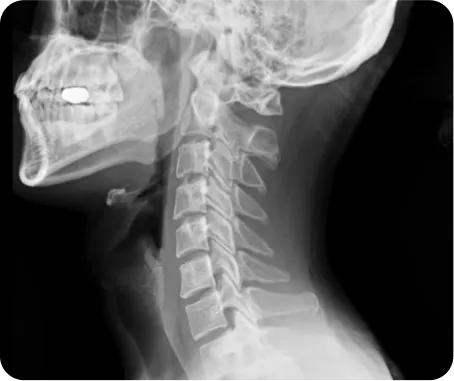

정상목 5kg

목뼈가 받는

하중

일자목 22.2kg

약 4.5배

일자목을 가진 사람이 받는 하중은

정상목의 약 4.5배이기 때문에

교통사고 시 발생하는 충격도

더 크게 발생하게 됩니다.

그래서 일자목인 환자의 교통사고 후유증 치료는

그 방법과 치료 기간이 다를 수밖에 없습니다.

연산당당한방병원은 척추관절을 교정하여

통증을 근본치료 해온 노하우를 담아

엑스레이 검사와 CT, MRI와 같은

영상의학적인 검사를 통해

교통사고 후유증 환자의 체형까지 고려하여

치료가 진행됩니다.